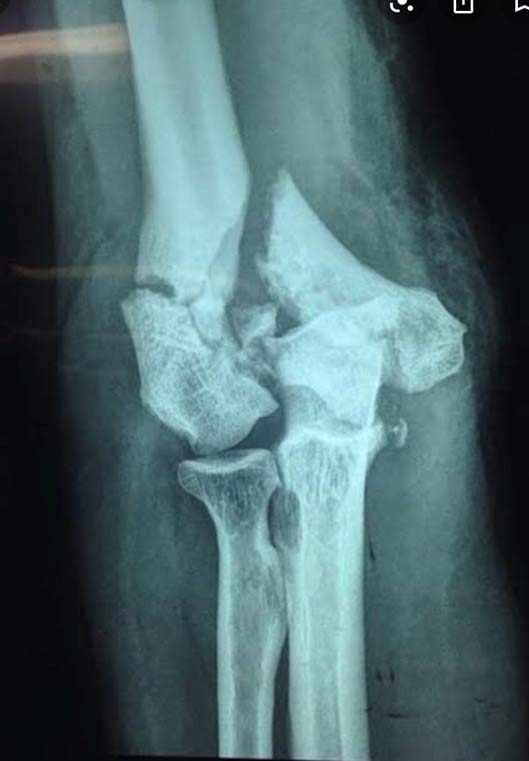

Fraturas do cotovelo

O cotovelo é composto por três ossos: o úmero, ulna e o rádio. As Fraturas do Cotovelo podem acontecer nesses três locais, isoladamente ou em conjunto, acompanhadas ou não por alguma lesão ligamentar ou de nervo. Assim como todas as fraturas, as de cotovelo se dão quando há um rompimento em um ou mais locais do osso. As que ocorrem nessa articulação são: a fratura da cabeça do rádio, a mais comum entre todas; fratura da porção distal do úmero e do olécrano (parte de trás do cotovelo, parte da ulna). As fraturas podem ocorrer em decorrência de uma queda com o braço estendido ou por traumas de alto impacto, como os acidentes automobilísticos. Dor, edema, hematoma e deformidade são os principais sintomas da doença. O diagnóstico e feito através da realização de radiografia e pela tomografia computadorizada. O tratamento pode ser realizado com imobilização gessada para aquelas fraturas bem alinhadas e o tratamento cirúrgico para as fraturas desalinhadas.